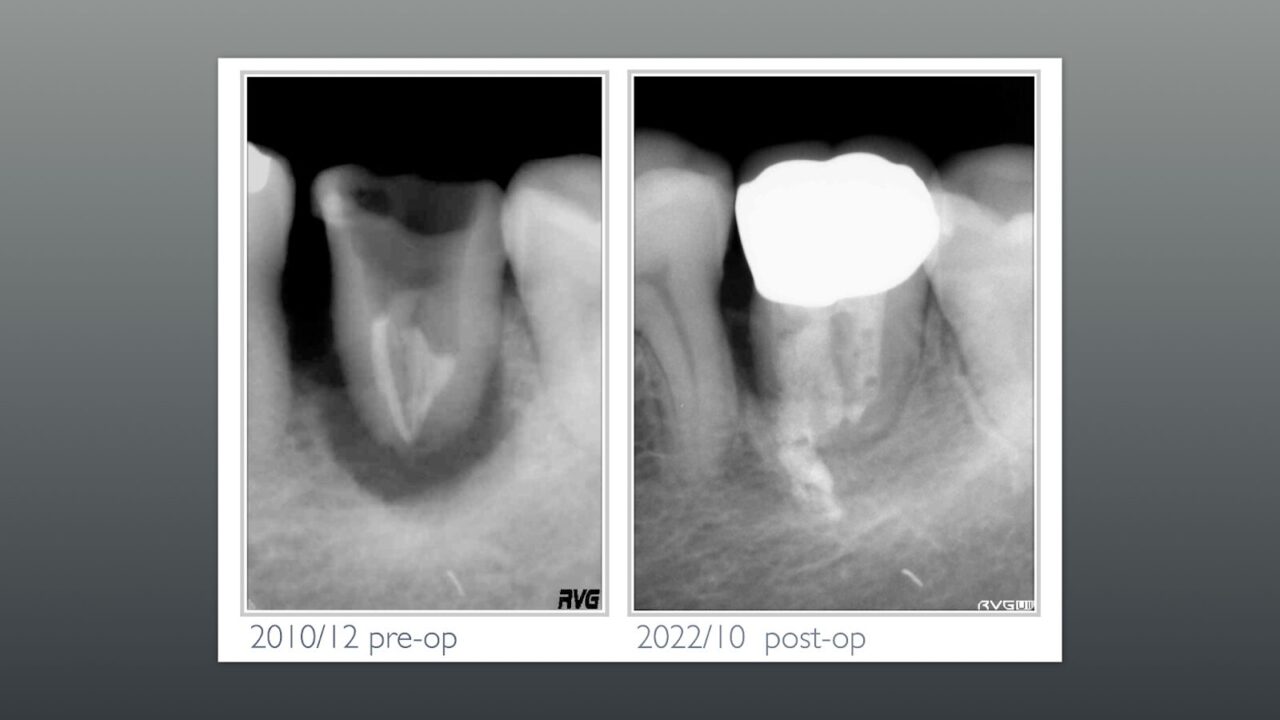

初診から12年後のレントゲン写真、近心には骨と思われるレントゲン像が確認できます。

術前のレントゲン写真との比較、頬の膿の道、サイナストラクトも閉鎖しいる事が確認できます。

2022/10が最後のリコールであるが、何も問題がないためリコールの来院にも応じていないと考えています。